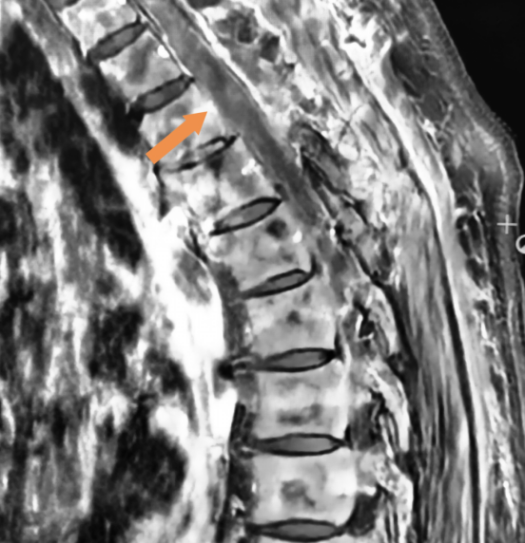

术后胸椎MRI增强检查

MRI平扫和增强是脊膜瘤的首选诊断方法,可以帮助我们确定肿瘤的边界及其与周围脊髓等神经结构的关系,是术前评估,术后确认是否充分切除以及肿瘤是否复发的可靠手段。脊膜瘤在MRI上特征性的图像为在增强MRI上出现的“硬膜尾征”,肿瘤局部的硬脊膜增厚,呈现线样强化并与肿瘤紧密相连。(图中黄色箭头像尾巴一样的亮线条就是“硬膜尾征”)